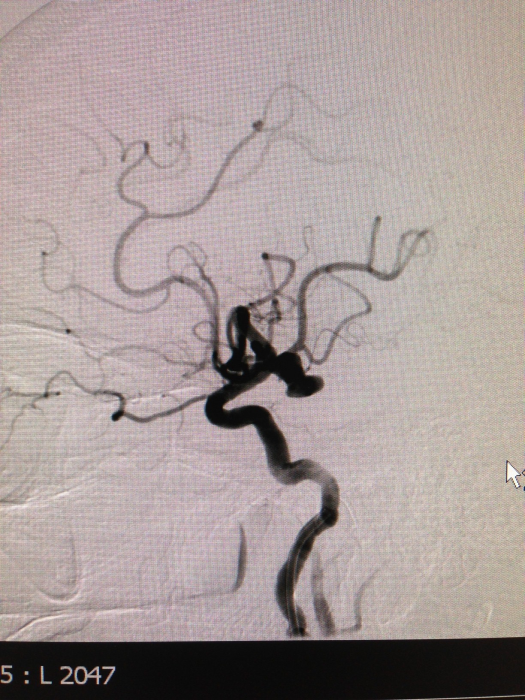

ما بعد عملية قسطرة المخ في المستشفى

تتمثل عملية قسطرة المخ بإدخال أنبوب من أحد شرايين الفخذ أو الذراع وأحيانًا الرقبة، ليتم بعد ذلك حقن صبغة تساعد في رؤية شرايين الدماغ والأوعية الدموية فيه عبر الشاشة الخارجية.

فحص تصوير الأوعية الدماغية (Cerebral angiography).

يمكن تشخيص هذا المرض فى المرضى  الأكبر سنا عن طريق الأشعة المقعية بالصبغة

كما يمكن اللجوء للقسطرة التشخيصية على شرايين وأوردة المخ لتأكيد التشخيص.

فى حالة حدوث نزيف من الناسور الشريانى الوريدى فيجب البدء بالعلاج فورا لأن إحتمالية حدوث نزيف قاتل تزيد بشكل كبيروذلك يتم عن طريق قسطرة المخ حيث يتم حقن مكان الناسور بمادة صمغية تغلق هذه الوصلة بين الشريان والوريد تماما.